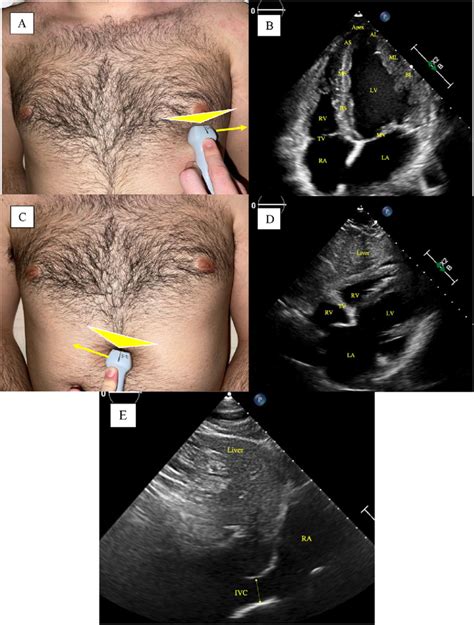

Hey guys! Today, we’re diving deep into a super crucial skill for anyone working with echocardiography: getting that perfect 5-chamber view . This isn’t just about ticking a box; it’s about understanding your patient’s heart from a unique angle that gives you invaluable information. We’ll break down exactly where to place that ultrasound probe to nail this view, why it’s so important, and what you should be looking for. So, grab your transducer, and let’s get started on optimizing your cardiac ultrasound skills! Understanding the fundamental views is the bedrock of proficient echocardiography. Among these, the five-chamber view stands out as a critical perspective, offering a comprehensive look at the left ventricle, left atrium, mitral valve, aortic valve, and the ascending aorta. Mastering its precise probe positioning is not just a technical skill; it’s an art form that directly impacts diagnostic accuracy. This view allows for the assessment of global left ventricular systolic function, evaluation of the mitral valve’s competence, and importantly, the visualization of the aortic valve in a way that complements other standard views like the parasternal long-axis view. When we talk about the 5-chamber view, we are essentially combining elements of the apical 4-chamber view and adding the aortic valve. This synergy provides a more complete picture, especially when dealing with complex congenital heart disease or assessing conditions affecting the aortic outflow tract. The probe, held in the operator’s hand, becomes an extension of their diagnostic intent. Its placement is not random; it’s a deliberate maneuver guided by anatomical knowledge and real-time imaging feedback. Achieving a clear 5-chamber view requires an understanding of the heart’s spatial orientation relative to the chest wall and the typical acoustic windows available. We’ll walk through the nuances of finding that sweet spot, ensuring you can confidently acquire this essential echocardiographic image. It’s all about optimizing the acoustic window, minimizing interference from lung or bone, and orienting the transducer correctly to capture the intended cardiac structures in their full glory. This article aims to demystify the process, making it accessible and actionable for all levels of sonographers and clinicians.

Alright team, let’s get down to the nitty-gritty of probe placement for that awesome 5-chamber view . This is where the magic happens, guys! You’ll typically want to start at the apical window . Think of the apex of the heart – that’s your target zone. Position the transducer at the left lateral chest wall , usually between the fifth and sixth intercostal spaces . Sometimes, you might need to go a little higher or lower, or more medially or laterally, depending on your patient’s body habitus. The key here is to aim the transducer towards the patient’s right shoulder . This orientation is super important because it allows the ultrasound beam to pass through the heart without being significantly blocked by the lungs or ribs. Imagine you’re trying to get a direct line of sight to the heart’s core. Now, the initial placement might give you a 4-chamber view. That’s a great starting point! From there, you’ll need to make subtle adjustments. The goal is to rotate the transducer slightly counter-clockwise (think of the indicator dot on the probe pointing towards the patient’s left axilla) while maintaining that apical position. This subtle rotation is what brings the aortic valve into view, effectively transforming your 4-chamber view into the coveted 5-chamber view. You’re essentially peeking over the left atrium to get a glimpse of the aortic outflow tract. Remember, you’re looking for a clear image of the left ventricle, left atrium, mitral valve, and the aortic valve, all in the same plane. The interventricular septum should be on your left, and the left atrial wall on your right. The aortic valve will be seen superiorly and slightly to the left of the mitral valve. Fine-tuning is everything. Small tilts and shifts can make a huge difference in image quality. Don’t be afraid to gently fan the transducer or adjust the depth and gain controls to optimize what you’re seeing. The goal is a symmetrical-looking left ventricle, with well-defined walls and clear visualization of all four chambers and the aortic valve. Practice makes perfect, so keep trying different angles and positions until it feels intuitive. You’ll know you’ve got it when you can see the mitral valve leaflets opening and closing, and the aortic valve opening during systole. This view is crucial for assessing mitral regurgitation, aortic stenosis, and the overall function of the left side of the heart. It’s the integration of anatomical understanding with hands-on manipulation that truly elevates your echocardiography skills. Patient positioning can also play a role; a left lateral decubitus position often facilitates better apical access. However, always adapt to the patient’s ability to tolerate different positions. The depth setting on the ultrasound machine is critical; you want to ensure the entire heart is displayed without excessive surrounding tissue. Similarly, the gain settings need careful adjustment to differentiate between the endocardium, myocardium, and blood pool, avoiding both under-gaining (poor visualization) and over-gaining (flash artifacts or loss of detail). Patience and persistence are your best friends here. It might take a few tries, or even a few minutes, to achieve the optimal view, especially in patients with certain body types or lung disease that can impede ultrasound transmission.